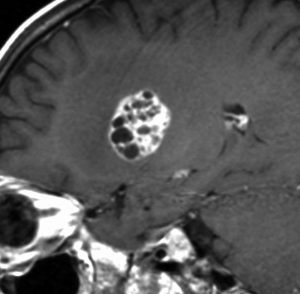

でも化学療法中に,右大脳基底核にあった腫瘍が増大して,左のMRIのように脳浮腫も悪化しました。この時点で患者さんが転院してきました。腫瘍マーカーは陰転していて,どう見ても奇形腫が化学療法によるparadoxical responseを生じたものでした。ジャーミノーマが消えて奇形腫だけ増大するという現象です。

まず手術で全摘出して,成熟期奇形腫の病理診断を確定しました。それからICE化学療法を2コース加えて,脳脊髄照射 24Gy12分割を行いました。

大脳基底核に胚細胞腫瘍がある場合には全脳照射が基本ですが,なぜ脊髄照射を加えたかということには絶対の根拠はありません。治療前のAFPがやや高く若干の播種性格を有する未熟奇形腫が手術前に消失していたかもしれないという可能性を考えたことと,発症が12歳ですから脊髄照射を24グレイ加えても重篤な遅発性障害が生じないと判断したからです。